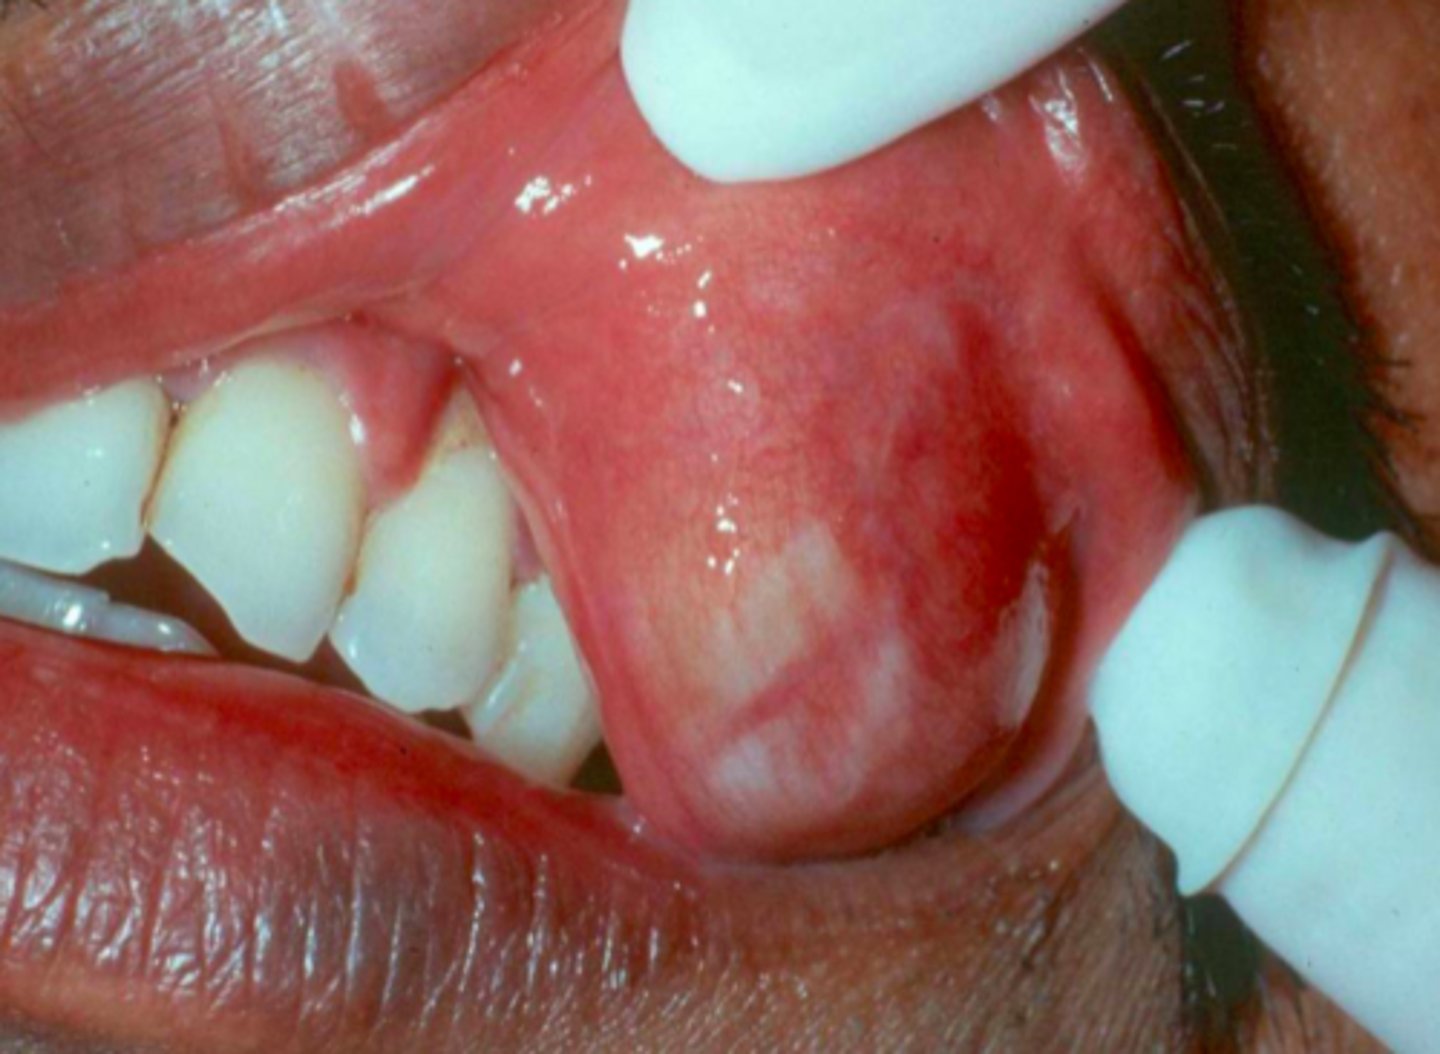

Necrotizing Sialometaplasia

Patient presents with single ulceration on the hard palatal mucosa. Patient claims it "used to be red and swollen, now it's like a crater". Histo path report reveals Acinar necrosis with preservation of lobular architecture, squamous metaplasia and Pseudoepitheliomatous hyperplasia. What is the diagnosis?

ID the pathology:

- Rare inflammatory, destructive condition of salivary glands

- Mimics malignancy clinically AND microscopically

- - Early swelling and erythema

- - Later ulceration

- Related to ischemia?

- Male predilection

- Initial swelling, then crater-like ulcer develops

- Rare destruction of palatal bone

hard palatal mucosa (75%)

The most common location for Necrotizing Sialometaplasia to present is the ______

ID the pathology based on the histology findings:

- Acinar necrosis with preservation of lobular architecture

- Squamous metaplasia

- Pseudoepitheliomatous hyperplasia

- Biopsy necessary to confirm diagnosis

- Resolves without treatment in 5-6 weeks

What is the treatment for Necrotizing Sialometaplasia?